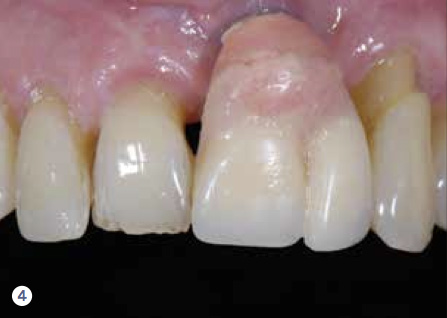

For example, consider the case of a 70+ year-old man who had been inappropriately treated with an implant-supported restoration. Although his lip position and mobility were satisfactory (Figure 3), the dentistry hidden beneath the restoration revealed the extent of poor implant placement and restoration design (Figure 4). Upon removal of the restoration, it was clear the implant was placed in the incorrect position from multiple perspectives—mesial-distal, buccal-lingual, apical-coronal, and angulation (Figure 5). Assessing priorities in this case required consideration of potential alternatives for redesigning the implant-supported restoration.

Fig 4. The retracted view reveals poor implant placement planning and restorative design.

Figure 4